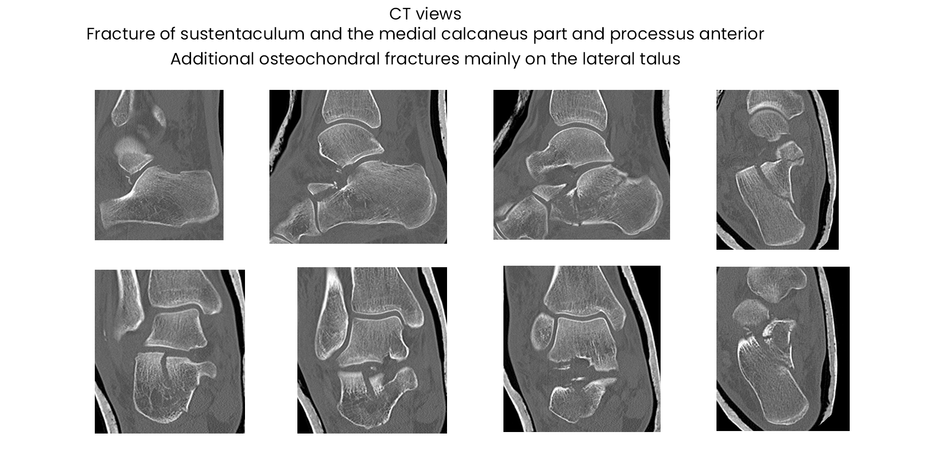

case 18ZJ, 23 years old, female, fall from horse, "atypical fracture" surgery after 2 days